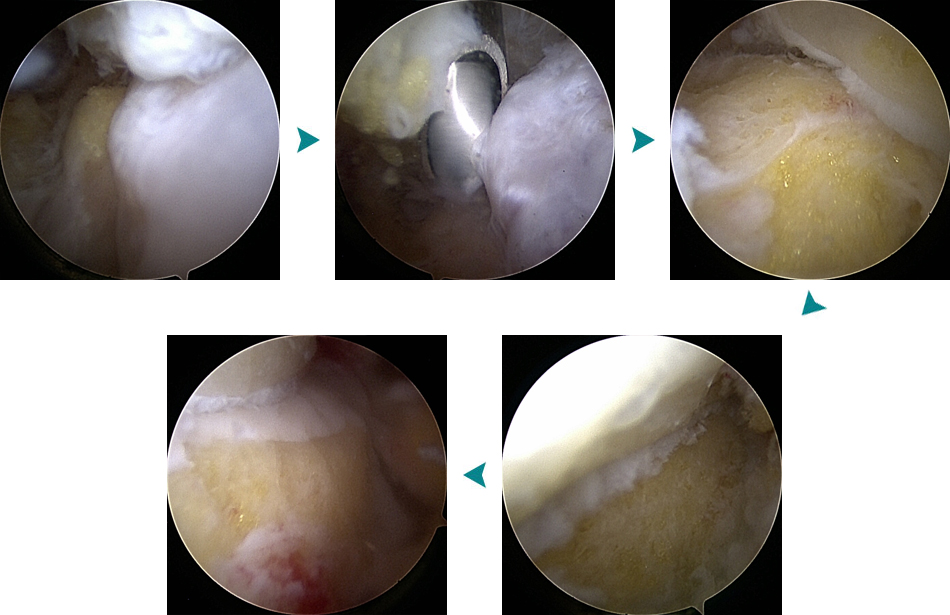

관절경 수술 - 전방 골극 제거 및 손상된 연부조직 절제 등

발목 전방충돌증후군

관절경하 골극절제술 / 연골성형술 및 미세절골술